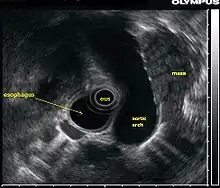

L’échographie endoscopique (EUS, acronyme de l'anglais Endoscopic ultrasound), appelée aussi ultrason endoscopique ou écho-endoscopie, est un acte médical qui emploie une source d’ultrasons au bout d’un endoscope relié à un échographe pour obtenir des images des organes internes de la poitrine et de l'abdomen. Elle peut être utilisée pour visualiser la paroi de ces organes ou pour examiner les structures adjacentes. Combiné avec l'échographie Doppler, le flux des vaisseaux sanguins avoisinants peut également être analysé.

L’échographie endoscopique s'applique le plus souvent sur le tractus digestif supérieur et sur le système respiratoire. La procédure est effectuée par les gastro-entérologues ou pneumologues qui ont eu une formation spécifique. La procédure ressemble à celle de l'endoscopie et peut être complétée par une biopsie écho-guidée.